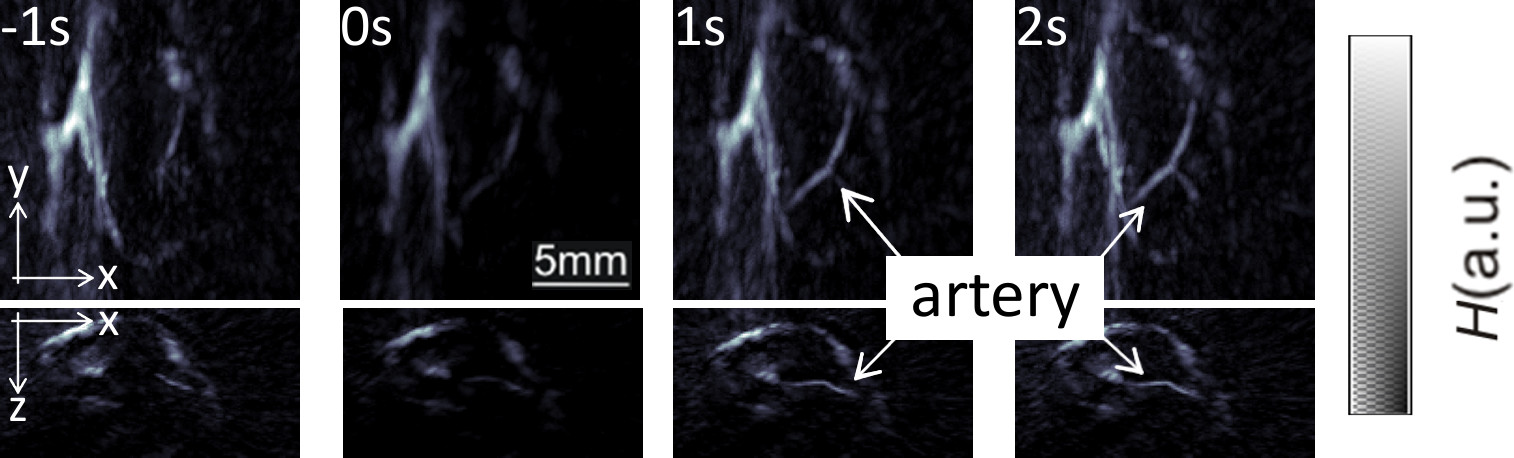

Figure 4 illustrates the capability of imaging dynamic processes in vivo. Herein, the circulation in the middle finger was obstructed by means of a rubber band and released during data acquisition18. A sequence of single wavelength images was acquired at 10 frames per sec as determined by the pulse repetition rate of the laser. Four MIP images along the lateral and depth directions spaced by 1 sec are showcased, where the second image corresponds to the instant after the circulation was restored. The wavelength was set to 900 nm, so that amplitude of the optoacoustic signals is increased both with blood volume and blood oxygenation.

Figure 4: Real-time imaging of blood flow. Maximum intensity projection images of optical absorption along the depth and lateral directions corresponding to four different instants. The circulation in the middle finger was blocked prior to the experiment and released during the experiment (at 0 sec). Please click here to view a larger version of this figure.